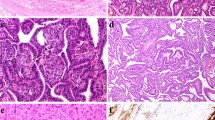

Immunostaining for pendrin was completely negative in PDS thyroid tissue of the four studied patients, as expected, in contrast to normal thyroid and Graves’ disease samples that were clearly immunostained at the apical border of the follicular epithelium (Fig. 3). In relation to the expression for the alternative-iodide exchangers ANO-1, CLC-5, and CFTR, we observed immunopositivity for all of them but mainly according to a cytoplasmic pattern, although with varying intensities (Fig. 3). Specifically, in Graves’ disease thyroid tissue the staining was slightly stronger than in normal thyroids, but rather similar to that displayed by hyperplastic areas of PDS thyroid tissue. Nevertheless, in HCFNs and follicular adenomas, the expression for the three antigens was clearly decreased or even negative (Fig. 3). Positive controls for ANO-1 (gallbladder and small intestine), CLC-5 (epididymis and kidney), and CFTR (larynx and gallbladder) were clearly immunostained.

Immunohistochemical staining for several iodide transporters (pendrin, ANO-1, CLC-5, and CFTR) in controls and PDS thyroid tissues. Normal thyroid (NT), Graves’ disease (GD), diffuse hyperplastic areas (DH) and follicular adenomas (FA) of PDS patients. In contrast to NT and GD, where immunostaining for pendrin is clearly located at the apical surface of follicular epithelium, no positivity for pendrin in PDS thyroid tissue is seen. Nevertheless, immunostainings for ANO-1, CLC-5, and CFTR are positive in hyperplastic areas of PDS thyroids, as it also occurs in GD tissue, although at cytoplasmic level. Conversely, follicular adenomas are negative. Scale bars, 25 µm

Distribution of PC in PDS thyroid tissue using double immunofluorescence (E-cadherin, green; acetylated α-tubulin, red; nuclear counterstaining with DAPI, blue). Numerous ciliated follicular cells are clearly identifiable in normal thyroid follicles (A), microfollicles (B), and papillary follicles (C) and much less evident in highly cellular follicular nodules (HCFNs) with microfollicular pattern (D). In contrast, only scarce follicular cells of HCFNs with spindle cells features (E) or trabecular follicular adenoma (F) show PC. Scale bars, 10 µm